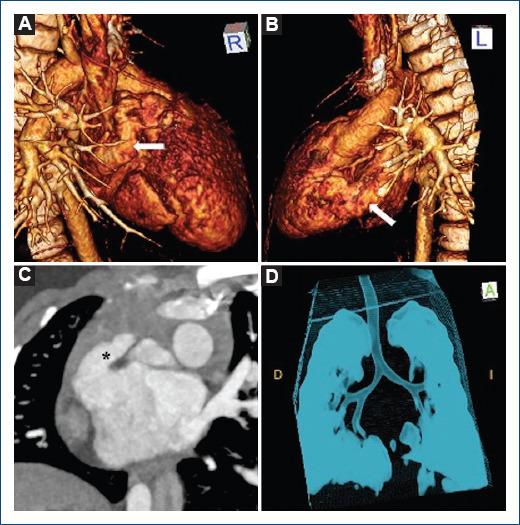

[心脏同构:一种多学科视角]

[Isomorfismo cardiaco: Una perspectiva multidisciplinaria].

Atrial isomerism describes complex anatomical findings with defects in the determination of lateralization; being a rare situation, with a prevalence of 1 in every 10.000 to 20.000 live births, with an incidence of up to 4% of all cardiac malformations. The diagnosis can be made in the neonatal age; however, clinical presentation is nonspecific. Depending on the spectrum of malformations, complex and invasive diagnostic tools may be required. Treatment is varied and can range from palliative surgery in view of univentricular physiology to total correction surgery for biventricular repair.

摘要

心房异构描述了在确定左右侧化方面存在缺陷的复杂解剖学发现;这是一种罕见情况,在每10000至20000例活产中发生率为1,占所有心脏畸形的比例高达4%。该诊断可在新生儿期做出;然而,临床表现并无特异性。根据畸形的范围,可能需要复杂且侵入性的诊断工具。治疗方法多样,从针对单心室生理状况的姑息性手术到双心室修复的完全矫正手术不等。